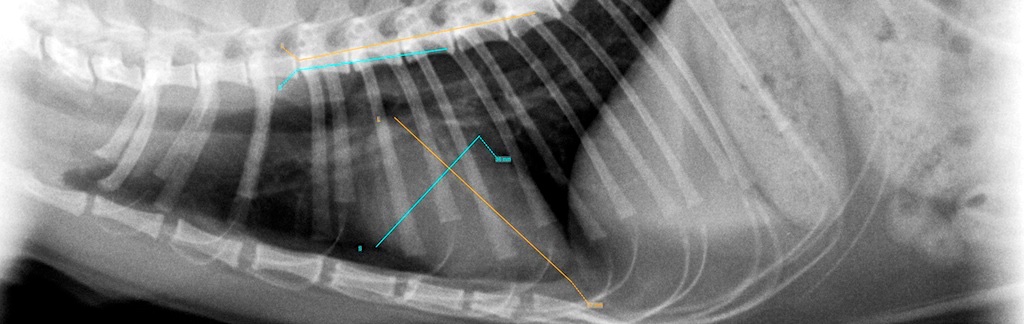

Röntgen

Seit dem Jahr 2000 Vertrauenstierarzt des SVÖ und HD/ED Röntgen- und Befundungsstelle für ÖKV betreute Hunderassen.